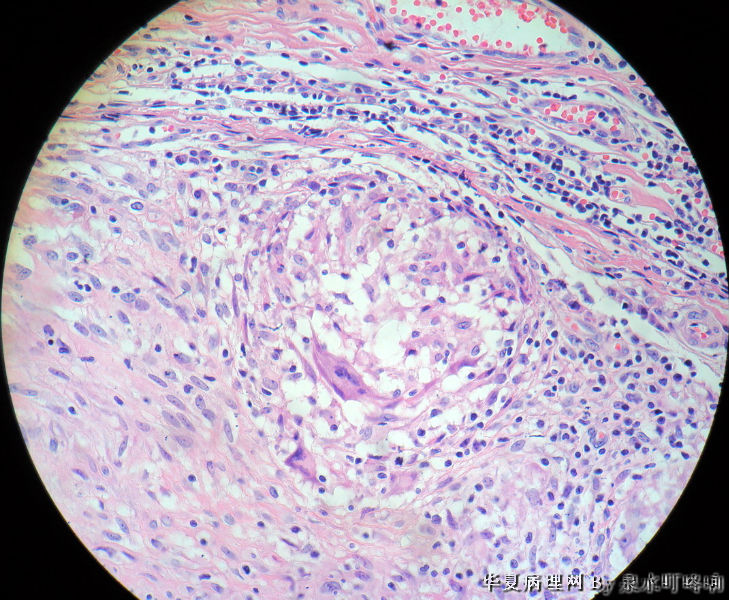

女,3岁,主因左腋窝肿物半年,术中见为肿大淋巴结,淋巴结内有脓液及坏死组织。

大体:灰红色组织一块,大小约4.6×3.5×2厘米,切面可见两个囊性区域,内容乳白色浓稠液体。